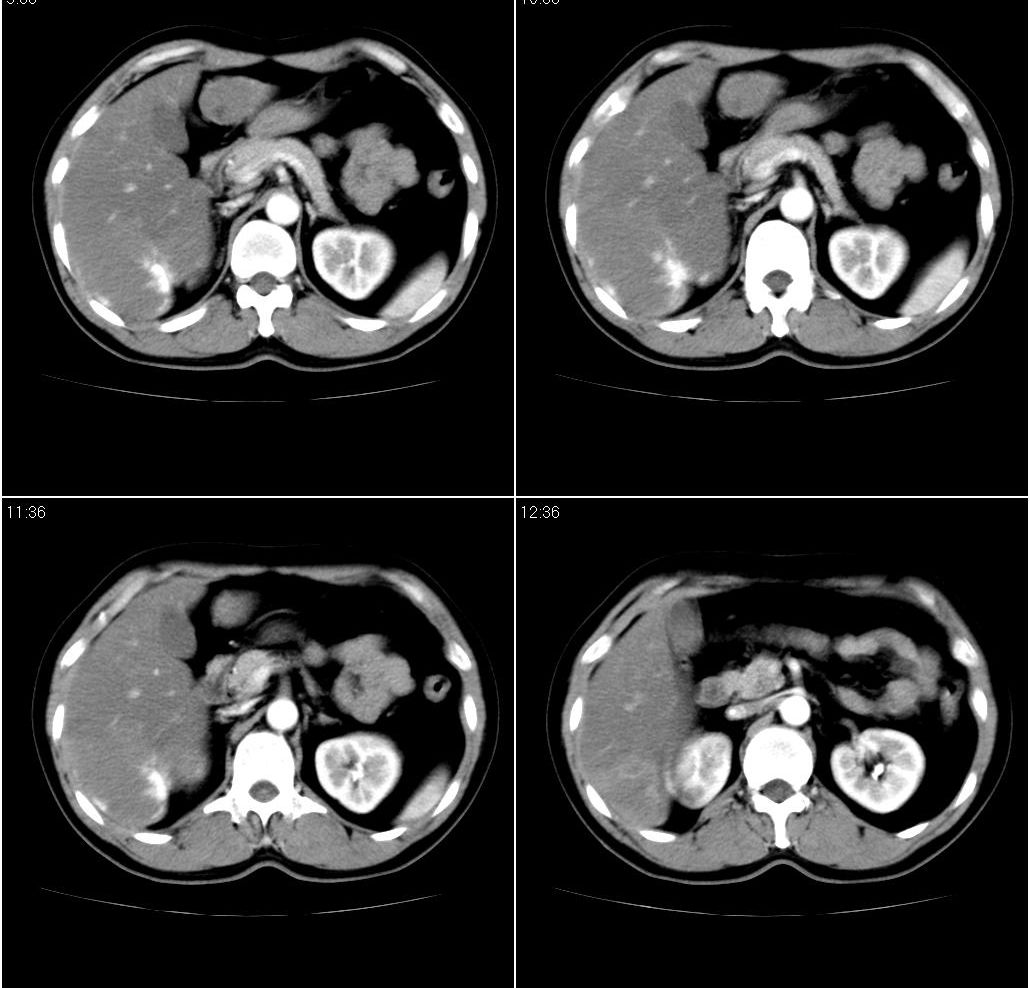

男,43岁。体检发现肝脏病变

肝右叶密度均匀减低,左叶增大,表面凹凸不平,内有低密度影。脾不大其密度较肝稍高。考虑1脂肪肝2肝左叶占位。建议增强。

肝右叶密度均匀减低,左叶增大,表面凹凸不平,内有低密度影。考虑1局灶性脂肪肝 2肝左叶占位。建议增强。

下缘与胃窦关系密切,会不会是来源于胃的间质瘤??

增强后诊断很明确了,缓慢结节样强化:肝内多发血管瘤